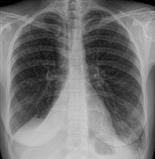

1. تصوير الصدر بالأشعة السينية

يظهر ارتشاح الرئة أبيض اللون في صور الأشعة السينية، بينما تبدو الفراغات الهوائية سوداء.

وقد يُجرى الطبيب المزيد من صور الأشعة السينية أثناء الاستلقاء على أحد جانبي الجسم، حيث أن هذا يمكن أن يُظهر ما إذا كان السائل يتدفق بحرية داخل الحيز الجنبي.